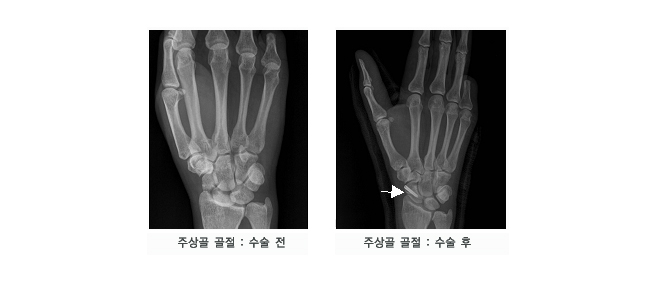

평상시 잘 사용하지 않던 몸을 사납게 사용하는 경우, 작은 바깥쪽 충격에도 뼈가 부러지는 등 골절을 겪기 쉬운 상태가 되요. 골절은 아무리 미세하고 약한 정도라도, 일상생활에 부담을 주고요.